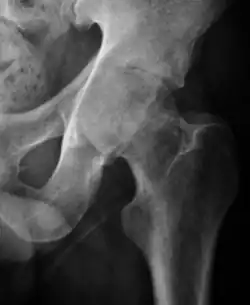

- Osteoarthritis

In adults, one of the main indications for radiographs is the detection of osteoarthritic changes (Figure 1(e)). Nevertheless, radiographs usually detect advanced osteoarthritis that can be graded according to the Tönnis classifications. The grading system ranges from 0 to 3, where 0 shows no sign of osteoarthritis. Intermediate grade 1 shows mild sclerosis of the head and acetabulum, slight joint space narrowing, and marginal osteophyte lipping. Grade 2 presents with small cysts in the femoral head or acetabulum, moderate joint space narrowing, and moderate loss of sphericity of the femoral head. Grade 3 is the severest form of osteoarthritis, which manifests as severe narrowing of the joint space, large subchondral cyst with productive bone changes that may lead to deformity of the bone components of the joint, while secondary osteoarthritis due to calcium pyrophosphate deposition can be diagnosed when calcification of hyaline cartilage and fibrocartilage is detected.[1]

There are other pathological conditions that can affect the hip joint and radiographs help to make the appropriate diagnosis. Acute bacterial septic arthritis can be diagnosed by radiographs when a fast regional osteoporosis and destructive monoarticular process develops (Figure 1(f)). In case of tuberculous or brucella arthritis it is manifested as a slow progressive process, and diagnosis may be delayed.[1]